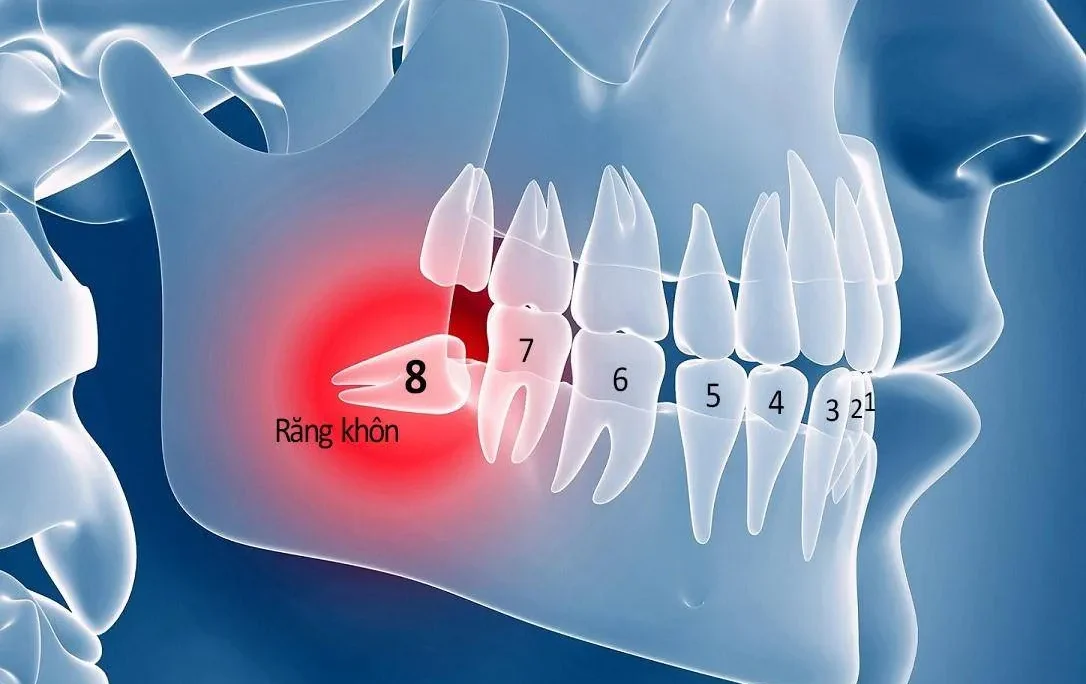

Răng khôn là chiếc răng cuối cùng được mọc lên phía trong cung hàm trên, dưới, trái, phải. Thông thường, mỗi chiếc răng khôn sẽ mọc 1 lần, tương ứng với 4 lần mọc 4 chiếc răng khôn khác nhau. Ngoài ra, thời gian để răng khôn mọc lên hoàn toàn thường rất lâu và mất thời gian dài. Thông thường thời gian mọc răng khôn từ vài tháng trở nên nên bạn có thể yên tâm.

Độ tuổi răng khôn thường mọc lên rơi vào khoảng 17-25 tuổi. Ban đầu mọc răng khôn thường khiến bạn cảm thấy khó chịu vì nó chọc sâu bên trong lợi. Từ đó gây bất tiện khi giao tiếp và ăn uống. Nếu răng mọc bình thường thì bạn không cần phải thực hiện nhổ răng. Tuy nhiên, một số trường hợp thì việc nhổ răng khôn là điều vô cùng cần thiết

- Những răng khôn có xu hướng đâm vào bên cạnh. Ví dụ như răng mọc ngầm, mọc lệch, đâm ngang, …

Thực tế, răng khôn là những chiếc răng mọc cuối cùng trong hàm, thuộc răng vĩnh viên. Lúc này, cấu trúc xương hàm đã ổn định hoàn toàn, phần nướu đã vững chắc và dày. Vì thế, răng khôn đã nhổ có mọc lên lại không thì câu trả lời là không. Sau khi nhổ răng khôn thì không có răng nào thay thế được tại vị trí này. Những chiếc răng vĩnh viễn này sẽ chỉ mọc 1 lần duy nhất trong suốt đời.

Tuy nhiên, một số trường hợp răng khôn đã nhổ nhưng kiểm tra lại vẫn thấy phần răng. Đây có thể là hậu quả của việc nhổ răng khôn bị sai cách hoặc bác sĩ chuyên môn kém. Nếu để lâu thì có thể dẫn tới việc sưng nướu và đau nhức.